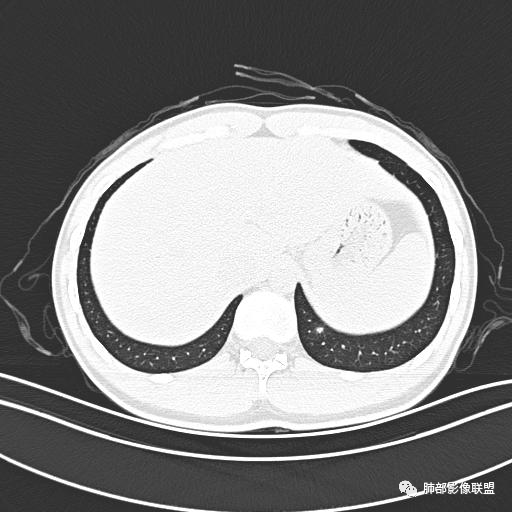

小强:青年,发热,皮疹;双肺散在结节,周围磨玻璃,点晕征,疱疹病毒感染,鉴别荚膜组织胞浆菌,结核。 大雄:青年,急性起病,发热伴全身皮疹2天,抗病毒治疗体温有下降。双肺随机分布大小不等类圆结节,“点晕征”。考虑水痘-疱疹病毒(VZV)血播询问接触史,查体皮疹分布以及形态基本可诊断。 王开金江津中心医院呼吸科:青年男性,起病急,病程短,以发热,皮疹为首发症状,感染指标以单核细胞升高为主,胸部ct双肺多发结界,周围有晕,点晕表现,随机分布,同意於老师意见,水痘疱疹病毒血流感染累及肺。 王秀仙:双肺多发大小不等结节,周围有晕,边缘模糊,呈点晕征表现。青年,急性起病,发热伴全身皮疹2天,抗病毒治疗体温有下降。考虑疱疹病毒。鉴别荚膜组织胞浆菌。 傅昌瑜:19岁男性,发热、全身皮疹2天,单核细胞增高,双肺多发结节,结节边缘见边界不清磨玻璃影。点晕征+发热、全身皮疹+单核细胞增高——考虑水痘-带状疱疹病毒肺炎。 一切∮随缘:年轻男性,发热,皮疹两天,实验室,CRP,PCT增高,影像:双肺多发散在磨玻璃结节,边界欠清,大小不等,呈点晕征改变,以血管束周围分布为主,局部血管束略增粗,其它无明显改变,考虑:1:病毒性肺炎(水痘疱疹病毒?不知道皮肤有无改变)2:真菌(组织胞浆菌,血管侵袭性肺曲霉)3:GPA4:寄生虫(实验室没有看到嗜酸细胞增高) 赵山河:双肺散在结节,周围有晕,边缘模糊,呈点晕征表现。青年,急性起病,发热伴全身皮疹2天,抗病毒治疗体温有下降。考虑水痘—疱疹病毒感染。洪桥爱:青年男性,发热、皮疹2天,伴瘙痒,皮疹于面部首发,之后进展至全身,虽然没有对皮疹进行描述,但是从出疹时间及皮疹进展情况,伴瘙痒,应该就是个水痘患者;CT提示双肺随机分布结节影,部分结节伴有边界不清晕征,考虑水痘血播肺。 刘强:年轻男性,急性起病,皮疹,发热,抗感染治疗体温下降,说明有效。影像表现为散在点晕征,感染类疾病谱(疱疹病毒,真菌,结核),结合年龄,皮肤皮疹,考虑水痘-疱疹病毒性肺炎。 小兜:男性,19岁,发热皮疹两天,颜面部至全身,CRP,降钙素及单核增高。CT示双肺散在小结节,周围伴磨玻璃影,点晕征,考虑为水痘-带状疱疹病毒(varicella-zoster virus,VZV)肺炎 必有路:青年,皮疹+发热+“点晕征”→水痘-疱疹病毒(VZV) 许慧良:青年男性患者,发热、皮疹2天,体温最高38.5℃,第3天皮疹扩展至全身,伴瘙痒,胸部CT:双肺多发随机分布的小结节,结节周边见边界模糊的晕征,考虑水痘病毒感染流心明智:男,19,急性起病,发热伴全身皮疹2天。出疹顺序头→全身,抗病毒有效。胸部CT:两肺多发大小不等类圆形实性小结节影,随机分布,结节周围环绕GGO,边界模糊,呈点晕征。出疹特点是关键,未提示。考虑:血播病毒性肺炎,水痘-疱疹病毒?麻疹?鉴别荚膜组织胞浆菌、TB、血管炎、寄生虫等。 浪迹天涯:病灶多为5-10mm大小结节,结节周围可见磨玻璃样的晕环,常多发,可分布于肺内任何区域,考虑水痘—带状疱疹病肺炎如果短时间内有新的一个区域浸润,更加能说明,